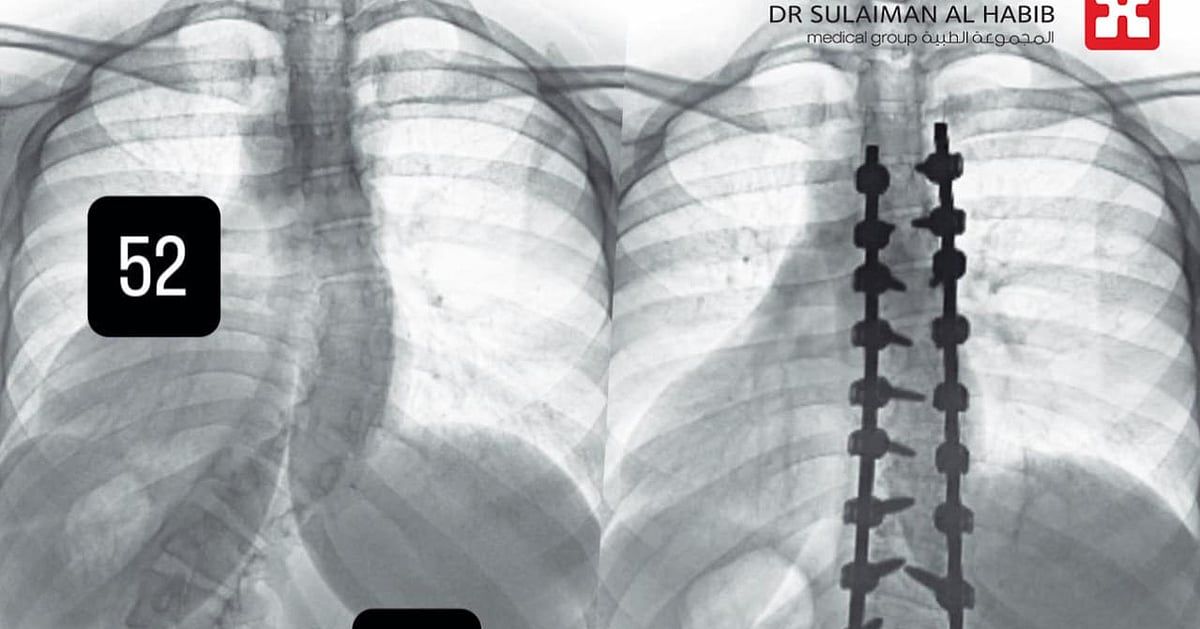

وأجرى لها الفريق الطبي، حزمة من التحاليل والفحوصات الطبية الدقيقة، التي بينت إصابتها بحالة انحراف بجنف درجته "52" بالفقرات الصدرية وآخر بدرجة "72" في الفقرات القطنية، ودرس الفريق الطبي الحالة على ضوء نتائج الفحوصات والتحاليل، وخلص إلى ضرورة التدخل الجراحي لعلاج العيوب، والحد من المضاعفات، وأخضعت الفتاة لعملية جراحية، تم فيها تقويم العمود الفقري بعدد "26" من البراغي والقضبان المعدنية من التايتانيوم والكوبالت والطعوم العظمية الصناعية وتثبيت ودمج الفقرات، وشارك في العملية التي استمرت لـ"6" ساعات، فريق تخدير وتمريض متمرس، واستخدمت فيها مجموعة من أحدث الأجهزة الطبية، التي ساهمت مع الكوادر الطبية عالية الكفاءة والتأهيل بالمستشفى في إنجاحها، ونقلت المريضة إلى جناح التنويم بعد العملية، حيث بدأت في التحسن بشكل متسارع بعد خروجها من غرفة العمليات، إذ استطاعت الوقوف والمشي خلال "24" ساعة، مع فريق العلاج الطبيعي المتمرس، كما أن طولها مع النجاح الكبير للتعديل زاد نحو "4" سم، وخرجت من المستشفى وهي بصحة جيدة، وتوقع أن تستعيد كامل القدرة على الحركة الطبيعية لاحقاً.